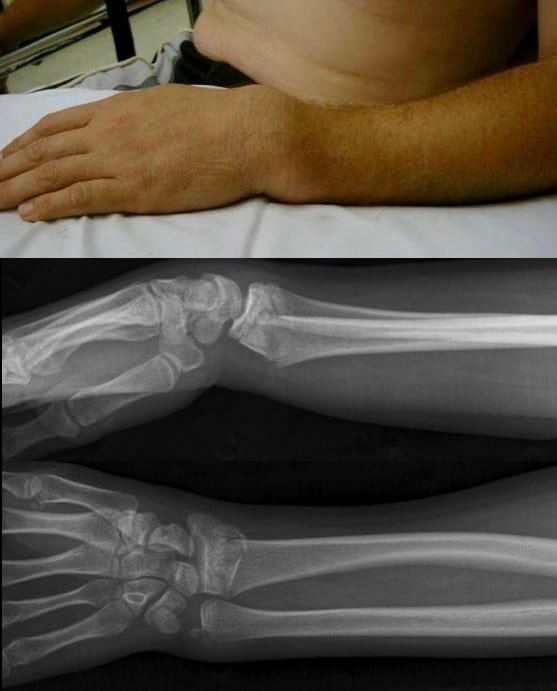

ايش هو ال colles fracture

هو كسر يحصل في ال radius bone لما الشخص يطيح ويحاول يمنع الطيحه بيده فيحمل ثقله كله على يده

هذا الكسر عادةً يسبب تشوه اسمه ال dinner fork deformity ? وسموه كذا لان يد المريض يسير شكلها زي الشوكة وسبب هالوضعية ان الشخص يطيح ويده واصابعه مفروده

ويعرف هالنوع من الاصابات بإسم FOOSH اختصارا لـ

"fallen onto an outstretched hand"